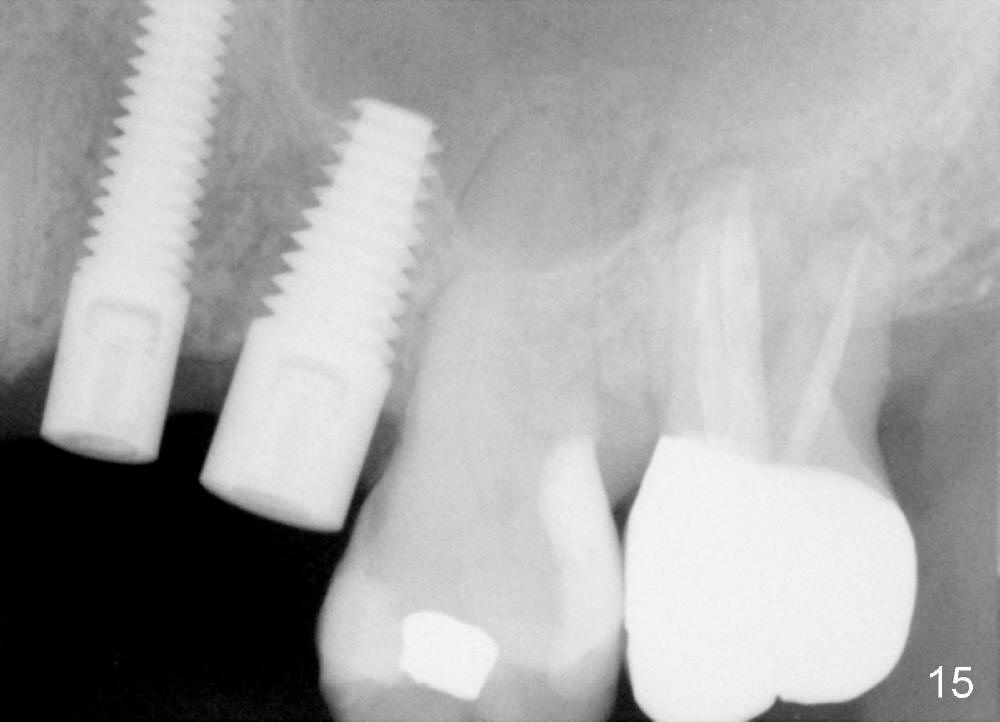

Three month follow-up shows that the gingiva and bone heal around these two implants (Fig.13-15).  Crowns are cemented 4.5 months postop (Fig.16).  There is no or minimal bone loss 9 months post cementation (Fig.17, as compared to Fig.15).  The bone is stable around the implants 18 months post cementation (Fig.18 panoramus).  Root canal therapy is done at #14 between the last follow up appointments.